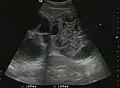

Liver cyst

Hydatid liver cyst. Diagnostic criteria are the presence of membranes and sediment inside.